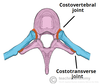

Transverse processes: These extend laterally and posteriorly away from the pedicles. In the thoracic vertebrae, the transverse processes articulate with the ribs.

Each thoracic vertebrae has two ‘demi facets‘ on each side of its vertebral body. These articulate with the head of the respective rib, and the rib inferior to it. On the transverse processes of the thoracic vertebrae there is a costal facet for articulation with its respective rib.